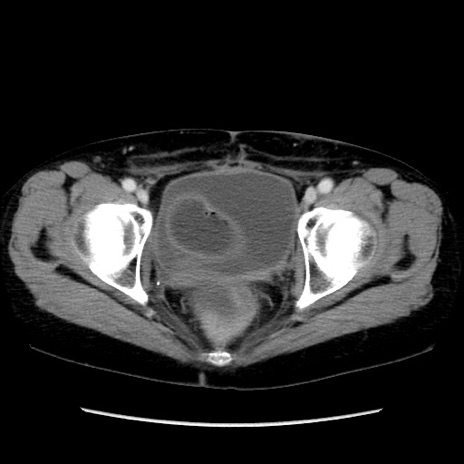

症例32(横断像)

【症例】40歳代 女性

【主訴】上腹部痛、嘔気・嘔吐

【現病歴】約9時間前頃から急に上腹部痛、嘔気、嘔吐が出現。改善しないため救急要請。

【既往歴】子宮頚癌(広汎子宮全摘術、放射線療法)、腸閉塞

【身体所見】腹部:平坦、軟、腸雑音亢進、上腹部を中心に腹部全体に圧痛あり。

【データ】WBC 8400、CRP 0.03